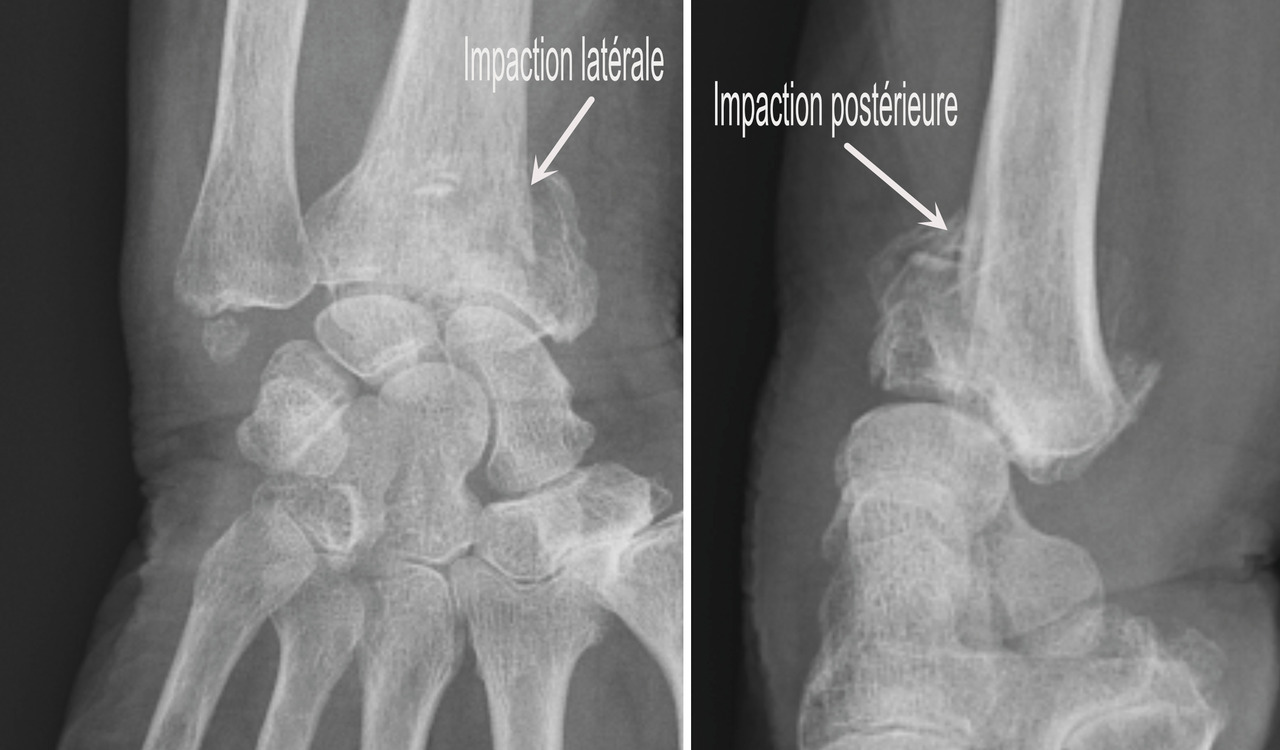

Au niveau métaphysaire le déplacement peut être postérieur ou antérieur (fig. 6). En ce qui concerne le déplacement postérieur, il est important de se souvenir que la surface articulaire regarde vers l’avant. En d’autres termes, dès que cela n’est plus le cas, même si la surface articulaire n’est pas orientée vers l’arrière, il s’agit d’un déplacement postérieur. Classiquement, le déplacement postérieur est lié à un mécanisme dit en compression-­extension, c’est-à-dire une chute sur la main, le poignet étant en extension (fig. 7). Le déplacement est dit antérieur s’il y a une exagération de l’orientation antérieure de l’épiphyse radiale. Ce déplacement est classiquement lié à un mécanisme dit en compression-flexion, c’est-à-dire une chute sur la main, le poignet étant en flexion (fig. 7). La plupart du temps, ce déplacement postérieur ou antérieur s’accompagne également d’un déplacement externe, avec un tassement au niveau de la corticale latérale (fig. 8). Outre le déplacement antérieur, postérieur ou latéral, il est très important d’analyser au niveau du foyer de fracture métaphysaire l’importance de la comminution qui peut être uniquement postérieure, ou antérieure, ou circonférentielle, ce qui conditionne la stabilité de la fracture et oriente vers le type d’ostéosynthèse à réaliser.